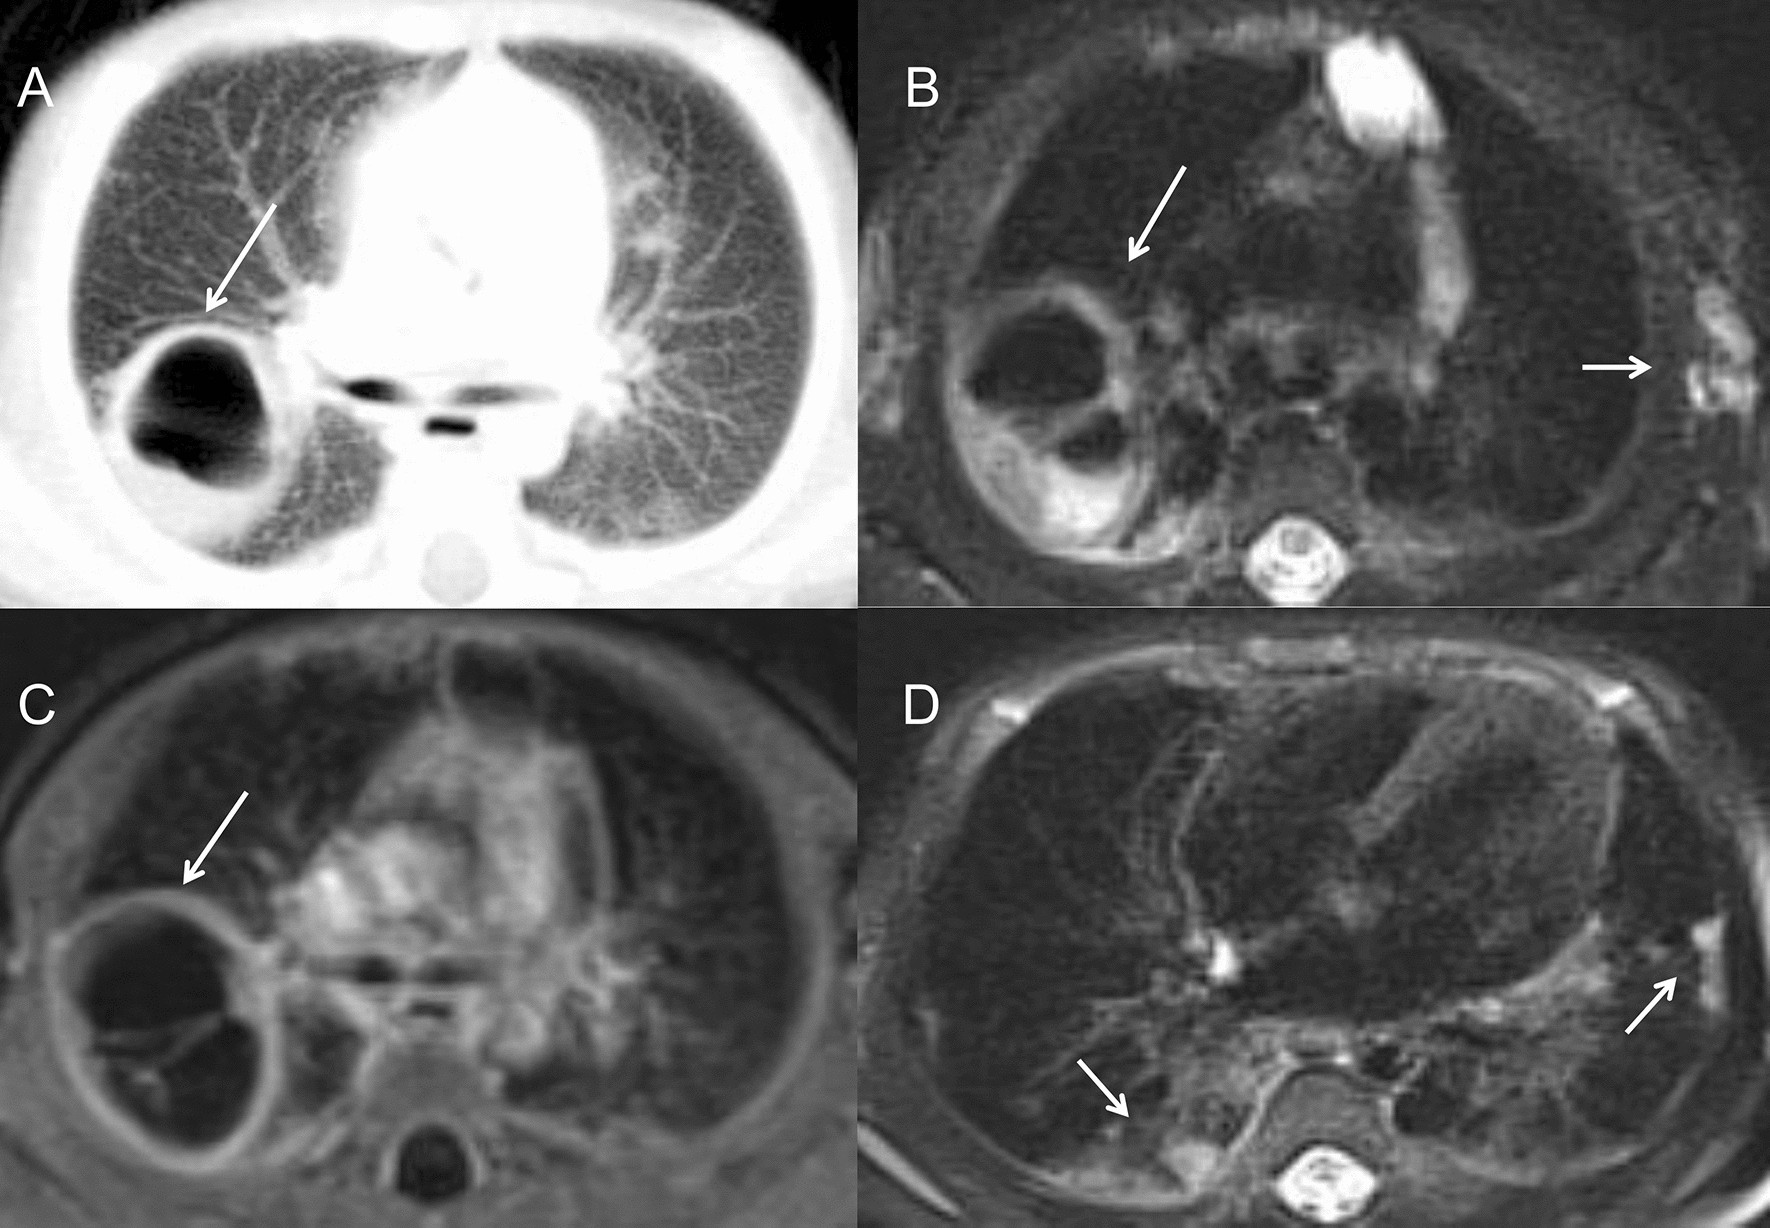

Figure 3

A 1-month-old boy with aspergillus infection. (A) On chest CT, a large cavity with thin and smooth wall was found in the right upper lobe, ranging 3 cm in diameter (long arrow). (B) On T2WI image, the linear separations and gas liquid leveling were found inside (long arrow). Multiple enlarged lymph nodes were found in the left axillary area (short arrow). (C) On post-contrast T1WI image, the wall of the cavity was obviously enhanced (long arrow). (D) Multiple pulmonary nodules were also seen in the bilateral lower lobe beneath the pleura (short arrow).